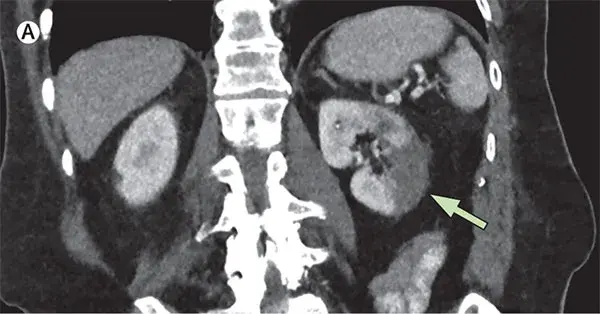

Uma causa incomum de hematúria glomerular intermitente!

Uma causa incomum de hematúria glomerular intermitente!

Hematúria pós infecção, caso clínicos para auxiliar no entendimento de causas glomerulares comuns e raras...